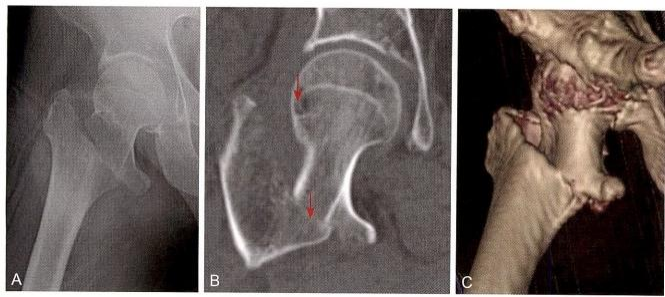

术毕透视,骨折复位质量优(4分),内固定稳定性优(7分)。术后 三维CT 证实仅前内下角获得骨皮质对骨皮质的可靠支撑。术后卧床2个 月,拍片发现前内侧角皮质愈合后开始扶双拐下地,1个月后扶单拐行 走。随访7个月,骨皮质愈合范围达到1/3周径,外侧壁也出现骨桥连接。 患者已去拐自由行走,功能良好(图9-22)。

图9-22 全转子区骨折。A.术前X线片,显示为31 A3型骨折;B 、C.术前三维CT示 骨折为全转子区骨折,分别有头颈骨块、股骨干骨块、小转子骨块、外侧壁骨块,前 壁骨块大转子分裂为前后2块;D~F. 采用mimics软件模拟骨折复位,显示骨折粉碎 程度